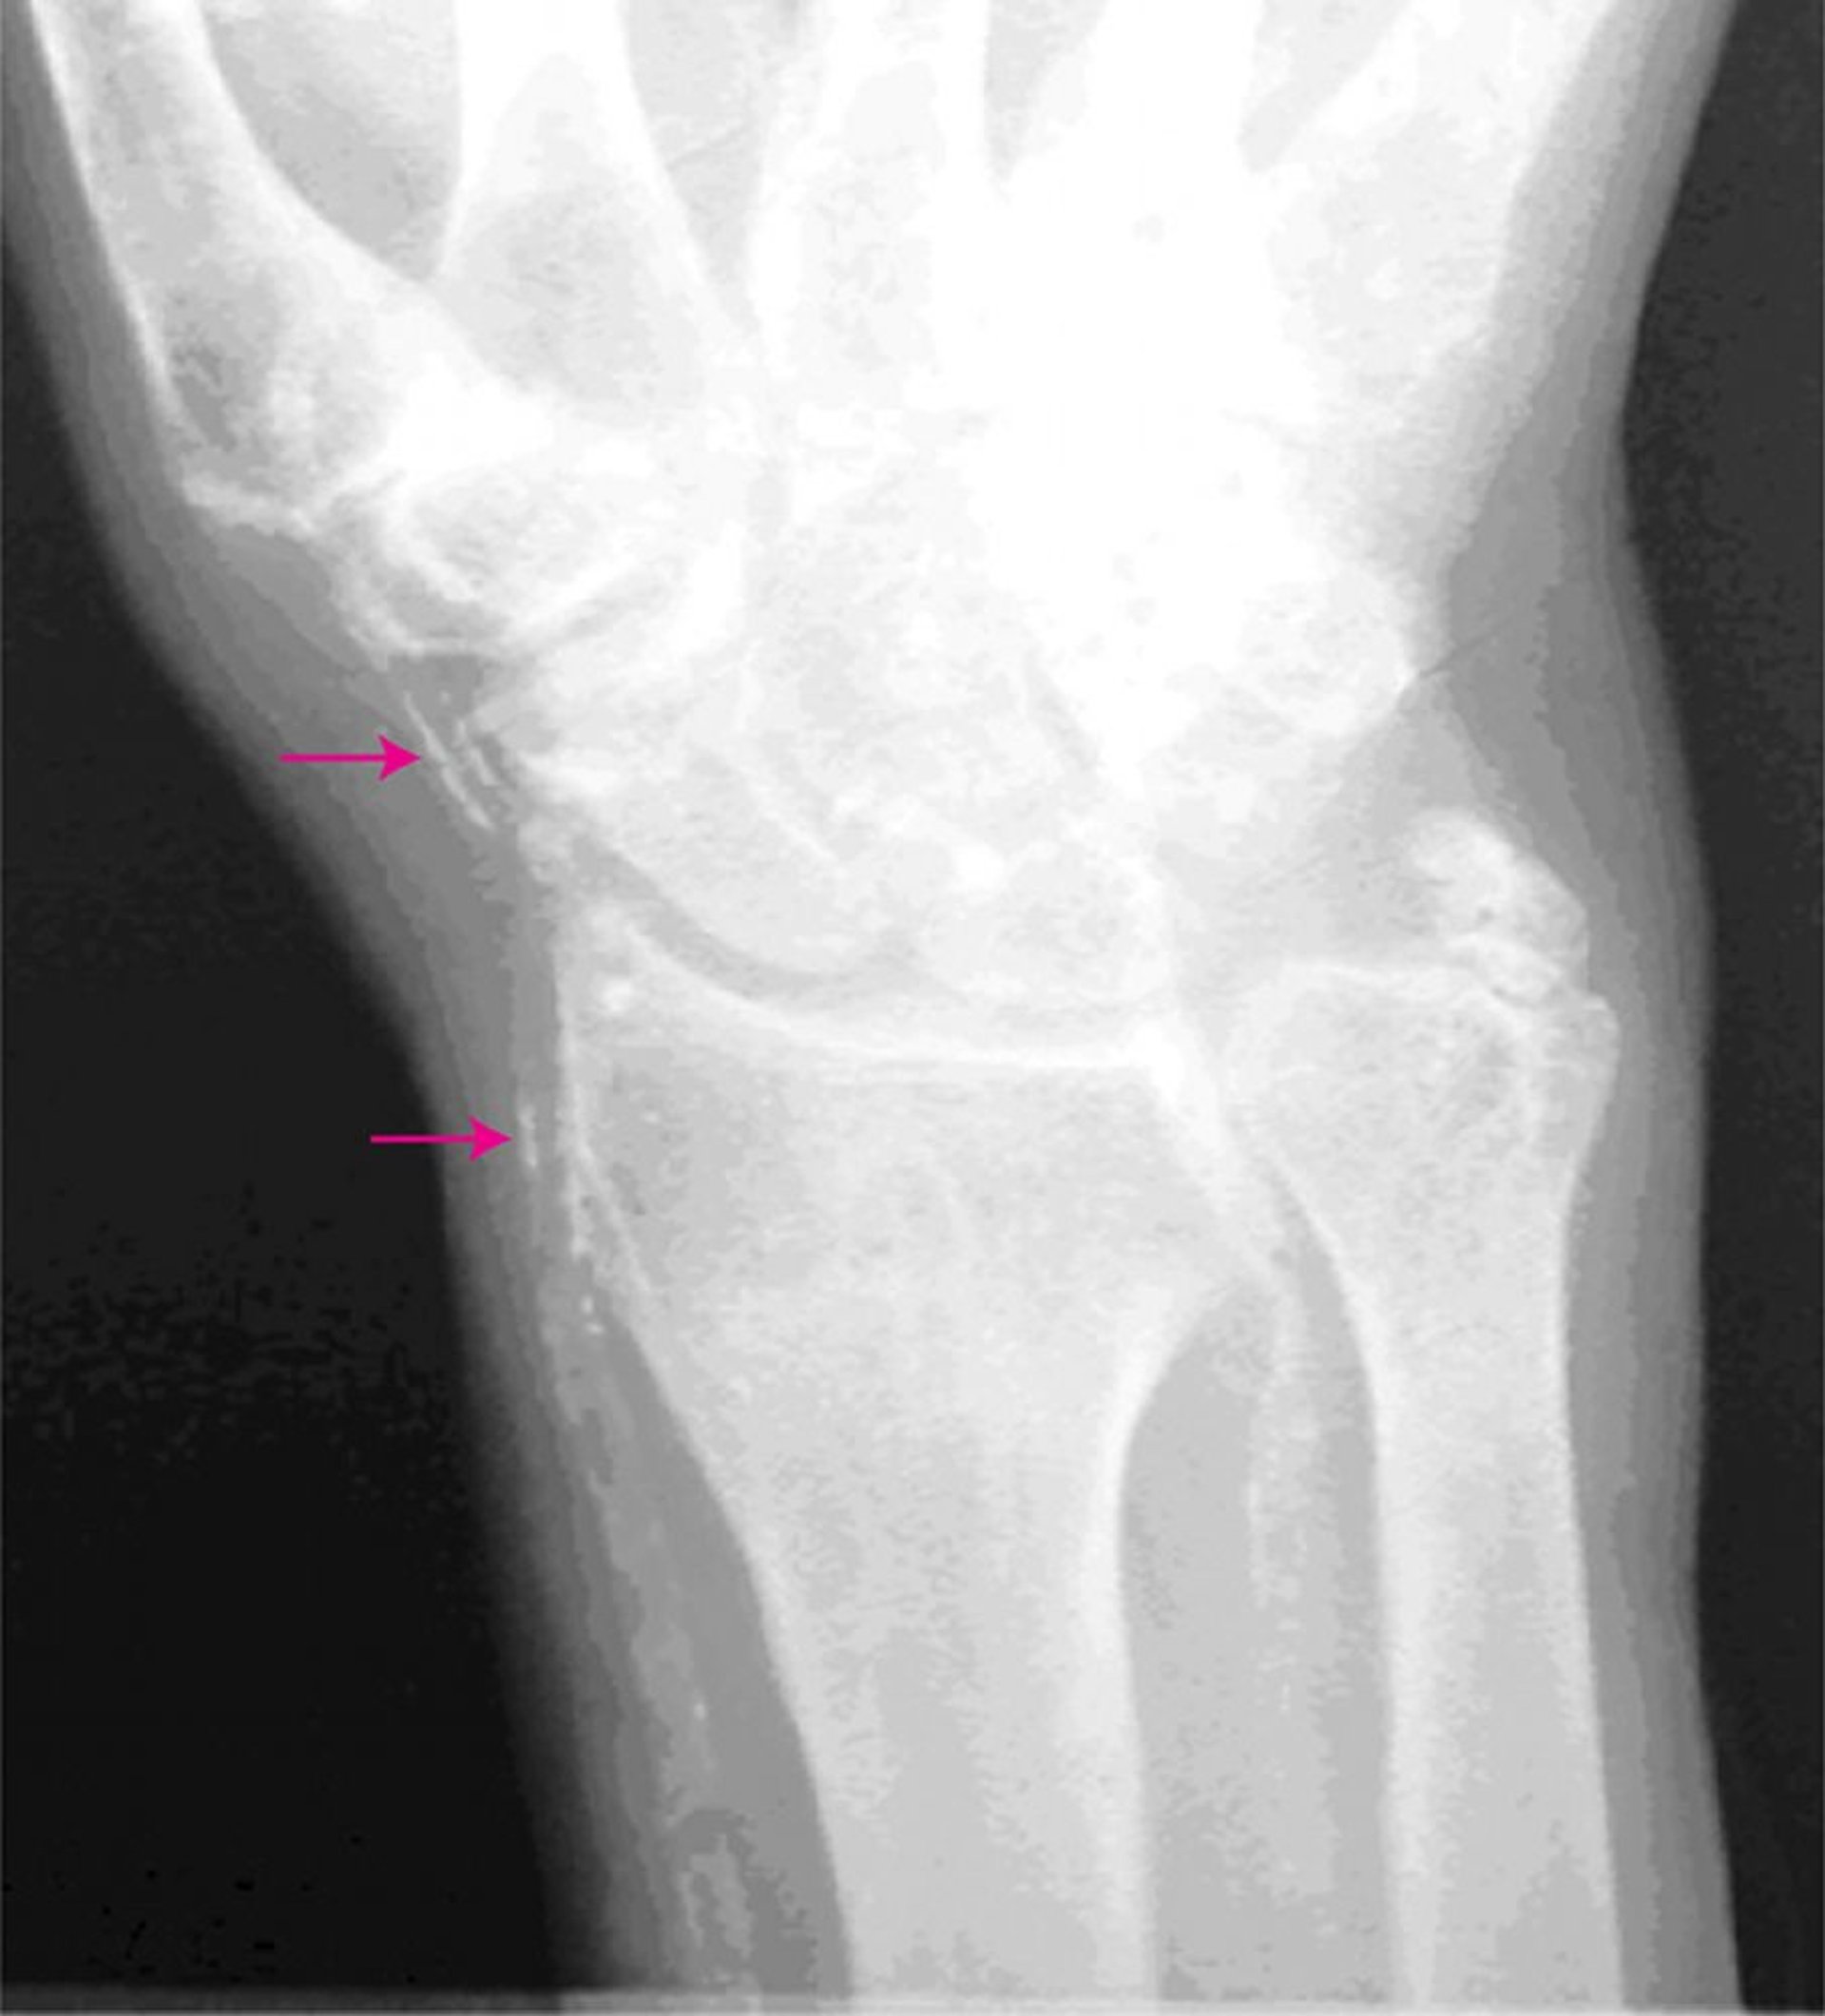

Artériosclérose de Mönckeberg

Cette radiographie de la main montre des artères calcifiées (flèches).